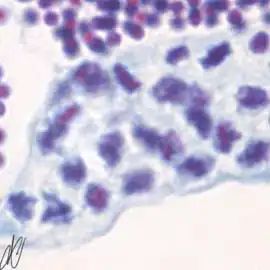

spermatogenesiscysts with successive stages of spermatogenesis in a seminiferous tubule | |||

| H&E | Putt's carbol fuchsin as a marker of spermatogenic maturation |

1. spermatogonium A (SgA) [arrows]: large single cell, with a large hypochromatic nucleus; early spermatogenic stages do not stain with Putt's carbol fuchsin. SgA divides mitotically to renew itself and to produce: |

2. early spermatogonium B (eSgB) [arrows]: morphologically indistinct from SgA, appears in clusters of 2-4 cells. Note a single Sertoli cell [red arrows], which are only occasionally observed; on the other hand, Sertoli cells are prominent after exposure to androgen or anti-androgen. |

3. early spermatogonium B (eSgB) [arrows in left image]: morphologically indistinct from SgA, appears in clusters of 2-4 cells; there is moderate mitotic activity in spermatogonium B, as indicated by PCNA immunostaining [arrows in right image]; in contrast, there is only very light PCNA immunostaining in the single spermatogonium A cell [red arrows in right image]. Early SgB divide mitotically to produce: |

4. late spermatogonium B: smaller than early SgB, clusters >4 cells [arrows in left image]; there is high mitotic activity, as indicated by the strong PCNA immunoreactivity [arrows in right image]. |

5. late spermatogonium B: clusters >4 cells [arrows]. Late SgB divides to yield smaller primary spermatocytes. Primary spermatocytes undergo meiosis, which consists of DNA duplication (yielding tetraploid cells: two copies of each chromosome, each copy consisting of two sister chromatids), genetic recombination, and two maturation divisions. The product of the first maturation division are secundary spermatocytes (diploid: one copy of each pair of chromosomes, consisting of two sister chromatids), the second maturation division yields spermatids (haploid). The first maturation division takes days, and therefore the successive stages of this division can easily be discerned: |

6. spermatocyte, leptotene stage of meiotic prophase ("threadlike" appearance of chromosomes). |

7. spermatocyte, leptotene stage of meiotic prophase, progressing to the zygotene stage; Note that there is staining with Putt's carbol fuchsin from this stage on, although still faint here. |

8. spermatocyte, zygotene stage of meiotic prophase ("bouquet" configuration of chromosomes) |

9. spermatocyte, zygotene stage of meiotic prophase ("umbrella" configuration of chromosomes). |

10. pachytene primary spermatocytes; in this stage, there is longitudinal contraction of the chromosomes, and the chromatin strands have a coarse appearance. |

11. dividing primary spermatocytes (diplotene stage); the metaphase, anaphase, and telophase of the first meiotic division (respectively equatorial arrangement of chromosomes, movement to cell poles, and actual division of the cell) are completed quickly, and are therefore only present briefly. The daughter cells of the first meiotic division are known as secundary spermatocytes (diploid). The second meiotic division is also completed quickly, and therefore secundary spermocytes are neither easily discernible. The resulting cells of the second meiotic division are: |

12. spermatids (haploid). |

13. spermatids. |

14. mature spermatozoa are released from open spermatocysts into the lumen of the tubules (spermiation). |